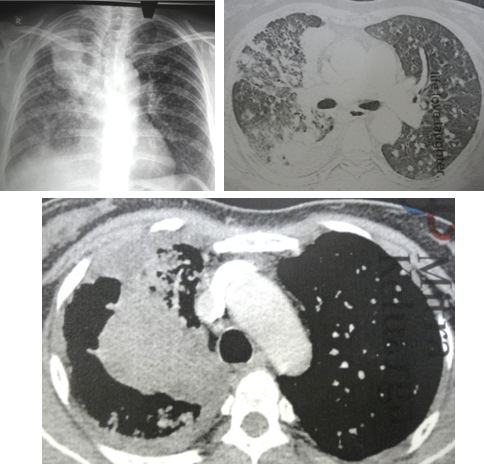

YN is a 54-year-old Indonesian lady. She had problems with her lungs. The doctor in Surabaya diagnosed it as TB. YN had been taking TB medication for the past seven months. Her condition did not improve.

YN then did a CT in May 2008.

The result showed:

• 8 x 5.5 x 5.5 cm mass in right lung.

• Segmental atelectasis, that is collapse of one or several segments of a lung lobe.

• Multiple subcentimeter nodule in both lungs.

• Subcentimeter lymphadenopathy (swelling of the lymph node).

• Fluid in the lung.

• Gallbladder stone.

• Thyroid lesion, 1.5 cm.

Having seen the CT scan (above) I explained to YN that taking our herbs would NOT cure her at all. To help her may be but to cure, no. YN understood this.

Looking at the scan and know her medical background, it appears to me that YN has metastatic lung cancer — I cannot figure out how the doctor ever diagnose her with TB.